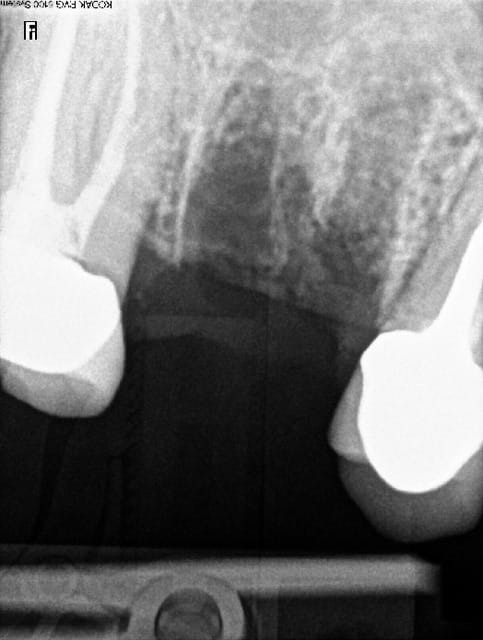

16 extraite, soulevé de la membrane sinusienne au piezo et pose d'un implant dans la foulée, comblement de l'alvéole au Bio-Oss.

un seul instrument un insert IM3 sur le mectron et je fais tout avec ça jusqu'à la membrane, normalement avec la pression d'eau qui sort de l'insert la membrane doit être soulevée.

j'aime pas utiliser les forêts dans le septum parce que souvent tu rippes.

pas de comblement au dessus de l'implant juste autour pour remplir l'alvéole.

parce que là j'ai 3 ou 4 mm d'os maxi.